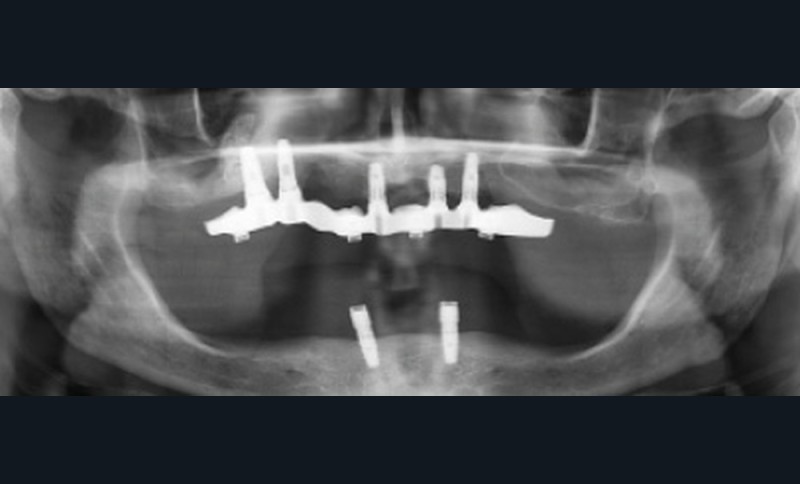

Une réhabilitation par PACSI maxillaire a été réalisée dix ans auparavant sur 5 implants en place de 13, 12, 21 et sur 24 et 26 (fig. 2a et b). Dans le cadre du plan de traitement initial, 6 implants avaient été indiqués. L’un d’entre eux, en position distale dans le secteur I, n’a jamais été ostéointégré. La patiente ne souhaitant plus de chirurgie, il avait donc été décidé de réaliser une prothèse sur 5 implants. La barre est directement connectée aux implants. À la mandibule, la patiente présente également une PACSI sur 2 implants associés à 2 piliers Locator®.

Lors de l’examen clinique, après dépose de la prothèse et dévissage de la barre, le constat est alarmant : présence de plaque abondante…